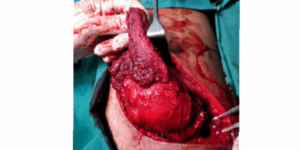

Pancreatic Tumour

Pancreatic Tumor